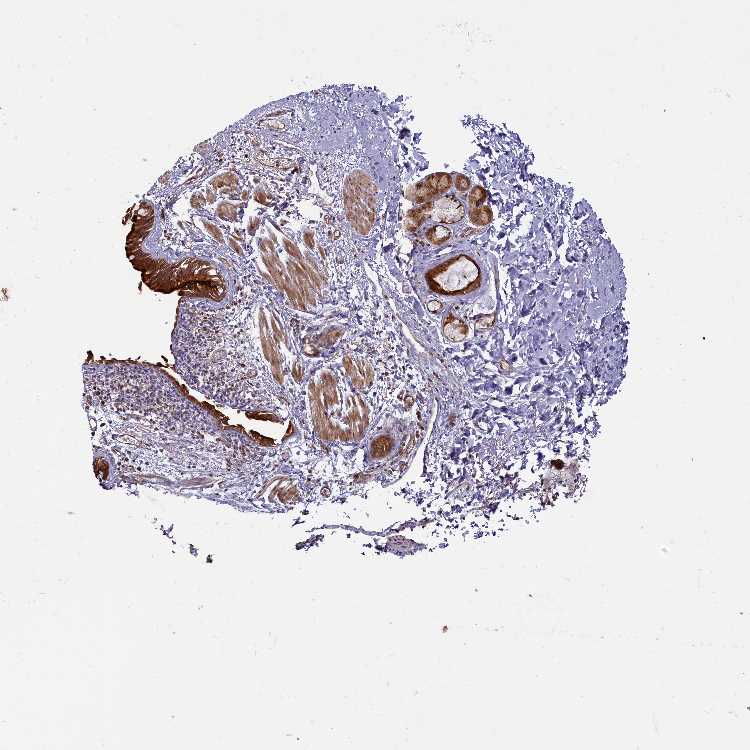

SOFT TISSUE 2 - Antibody stainingi

Antibody staining in the annotated cell types in the current human tissue is reported as not detected, low, medium, or high, based on conventional immunohistochemistry profiling in selected tissues. This score is based on the combination of the staining intensity and fraction of stained cells.

Each image is clickable and will lead to virtual microscopy that enables deeper exploration of all samples and also displays staining intensity scores, fraction scores and subcellular localization as well as patient and tissue information for each sample.

Antibody HPA041188

Fibroblasts Medium

Peripheral nerve Low